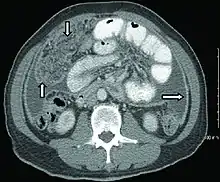

Extrapulmonary tuberculosis

Peritoneal tuberculosis may mimic peritoneal carcinomatosis on CT scan.[4]